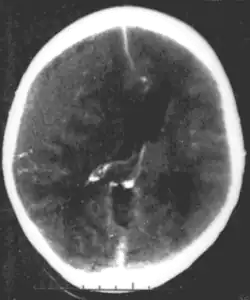

![]() Nieurazowy krwiak nadtwardówkowy u młodej kobiety. Szary obszar w górnej lewej części to organizujący się krwiak powodujący przesunięcie linii środkowej oraz uciśnięcie komór | |

Badaniem z wyboru przy podejrzeniu krwiaka nadtwardówkowego jest tomografia komputerowa. W TK widoczny jest krwiak o soczewkowatym kształcie i niekiedy szczelina złamania kości.